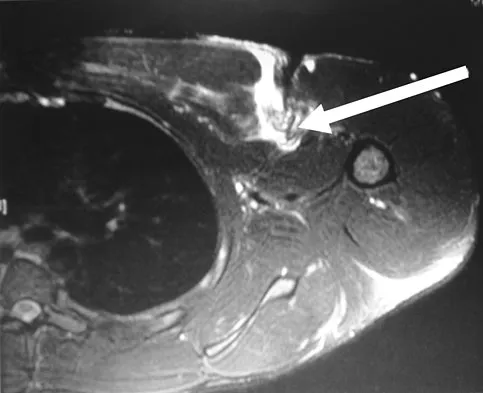

Question 13

Figure 42 is a transverse MRI scan of the left shoulder. The arrow points to which of the following structures?

Explanation